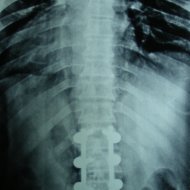

Omurga Kırığı

Omurga kırıkları osteoporozun olmadığı sağlıklı kişilerde trafik kazası ya da yüksekten düşme gibi yüksek enerjili travmalar sonucu oluşur. Eğer omurilik basısına neden olursa kısmi ya da tam felç ile sonuçlanabilir.

Eğer travma ilerleyen dönemde deformiteye yol açmayacaksa veya sinirlere baskı yaparak nörolojik bulguya neden olmadıysa korse ile tedavi edilebilir. Bu amaçla sert polietilen korseler ya da metalden yapılmış çerçeve tipi korseler kullanılabilir. Omurganın ağır zarar gördüğü durumlarda ileride oluşabilecek deformiteyi engellemek için omurganın vida ve çubuklarla sabitlenmesi gerekebilir. Nörolojik bulgu oluşturan bir kemiksel bası varsa, aynı seansta bu bası da ortadan kaldırılabilir.